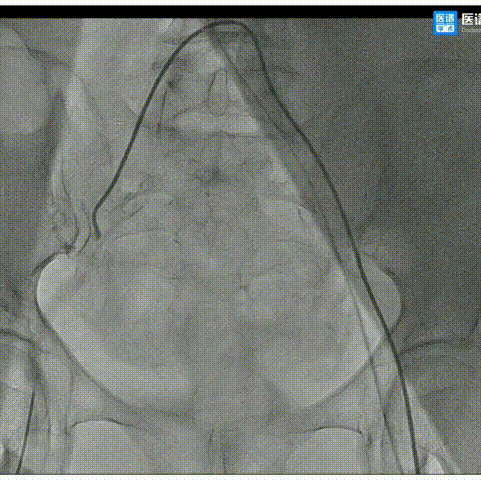

主动脉根部评估:

三叶式主动脉瓣 瓣环周长67.4mm

平均周长径21.5mm

左冠脉开口高度>瓣叶长度

综合瓦氏窦结构及瓣叶长度考虑

STJ平面周长83.5mm

升主动脉最大直径34.6mm

左冠高度15.0mm 右冠高度14.7mm

右冠脉开口高度>瓣叶长度

SOV瓦式窦:平均周长径 32.0mm

LVOT最短径14.6mm

术中仍球囊预扩须密切注意冠脉灌注

瓣叶轻度钙化增厚,钙化分布较均匀

HU752 积分271mm²

主动脉弓角度与宽度可,心脏水平夹角56°,近横位心。

外周血管内散见钙化灶,双侧入路血管内径良好,整体入路血管条件较好。

左室腔内径偏小,心室壁增厚明显。